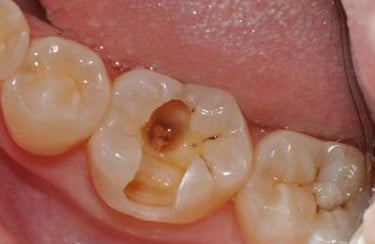

Caries Radicular

La caries radicular es la descomposición del cemento y la dentina en la raíz del diente, común en personas mayores con recesión gingival.

Los pacientes pueden experimentar sensibilidad y dolor en la raíz expuesta.

El tratamiento incluye la eliminación de la caries y la restauración de la raíz. La prevención incluye una buena higiene oral y el uso de flúor.